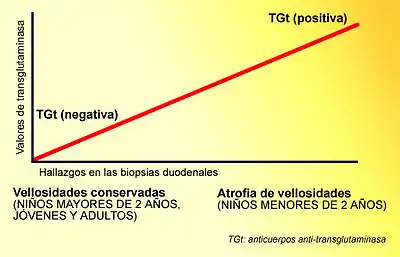

A diferencia de los criterios habitualmente utilizados por los expertos, las lesiones que la enfermedad celiaca provoca en el intestino delgado se limitan habitualmente a la presencia de una inflamación crónica de la mucosa duodenal, constituida principalmente por linfocitos, sin atrofia de las vellosides intestinales, especialmente en los niños mayores de dos años y los adultos. Actualmente, la presencia de atrofia de las vellosidades se considera un hallazgo menos frecuente.[19][50][51][52][40][53] También en contraposición de los criterios habitualmente empleados en la práctica clínica diaria, actualmente está reconocido que la celiaquía cursa frecuentemente con serología negativa (ausencia de anticuerpos específicos en sangre), especialmente la anti-transglutaminasa.[19][50][40][54][55][56][57] Esto se debe a que la anti-transglutaminasa se produce en la mucosa del intestino y con frecuencia, permanece depositada en ella sin pasar a la sangre.[20] [26][58] [59] Su evaluación en las biopsias duodenales es un nuevo método diagnóstico, que puede ayudar a detectar la enfermedad, pero es una técnica compleja, engorrosa y cara, por lo que su empleo no está generalizado en la práctica clínica habitual.[40][60][61] Esta prueba ha sido incluida en 2018 en España, como parte del nuevo protocolo para el diagnóstico precoz de la enfermedad celíaca.[62]

Cursa frecuentemente con serología negativa (ausencia de anticuerpos específicos en sangre), especialmente la anti-transglutaminasa,[19][50][40] ya que está elevada en relación con la presencia de atrofia de vellosidades, que no se encuentra en jóvenes ni en adultos por lo general.[40][53][54][55][56][57]

Los anticuerpos anti-trasnglutaminasa son positivos aproximadamente en el 90 % de los casos en los que hay atrofia marcada de las vellosidades intestinales. Sin embargo, solo son positivos en el 10-20 % de los celiacos que tienen inflamación intestinal sin atrofia de vellosidades, que son las presentaciones de la enfermedad que predominan en niños mayores de 2 años y adultos, por lo que es muy frecuente el hecho de encontrar una gran mayoría de casos de enfermedad celíaca con serología negativa.[55] [148]

Existe una relación directa entre la positividad de los anticuerpos anti-TGt y el grado de atrofia vellositaria presente en la mucosa duodenal, de tal manera que un mayor grado de atrofia, se corresponde con una mayor positividad de anticuerpos, como ocurre en las formas clásicas, predominantes en niños pequeños (menores de 2 años).[41] Por el contrario, cuando la biopsia duodenal es normal, o bien muestra cambios mínimos o presenta un grado de atrofia leve, los anticuerpos anti-TGt pueden ser negativos, como ocurre con frecuencia en los niños mayores de 2 años y adultos, en quienes predominan las formas no clásicas.[148][157]